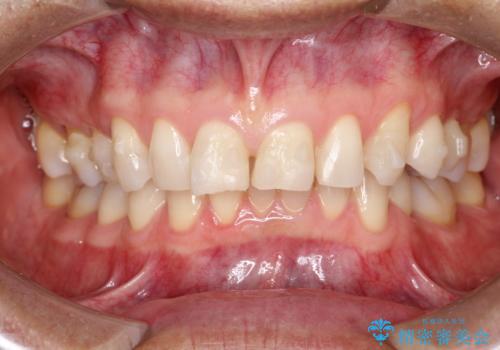

上の前歯の隙間とがたつきをインビザラインできれいな歯並びへ

- 以前矯正治療を他院にて行っており、最近上顎の隙間とガタガタが気になるとのことで来院されました。

上顎のみインビザラインにて矯正治療を行うこととなりました。

使用時間を守っていただけたので、比較的スムーズに矯正を終了することができました。